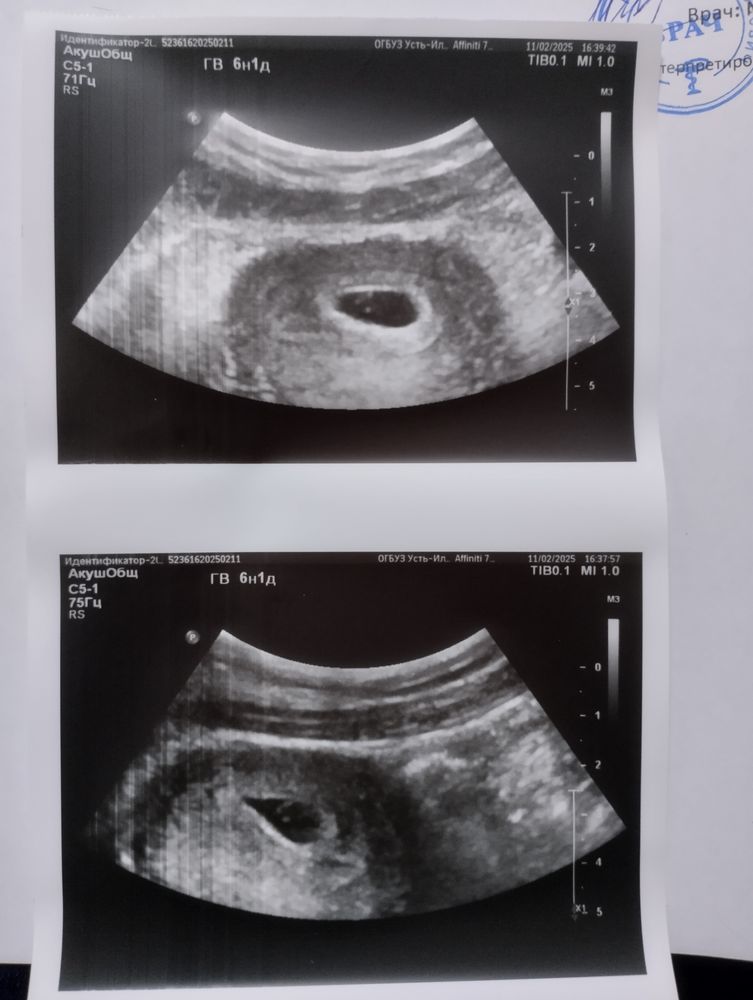

София в Зачатие 10 месяцев Непередаваемые ощущения 🥰 УЗИ Наше первое узи🎉 видела как бьётся его сердечко😍 сказали что все отлично и соответствует сроку❤️ Посмотрите еще 20 записей на эту тему Лучший ответ DyaNa Как здорово! Как радостно!! Пусть и дальше все будет легко, ладно-складно и в срок!!)))) 11.02.2025 Ответить София DyaNa, какие теплые слова🤗 спасибо) 11.02.2025 Ответить Отменить Ответить Майя Поздравляю Вас🤗🤞 11.02.2025 Ответить София Майя, спасибо большое 🩷 11.02.2025 Ответить Отслойка плаценты 10-я неделя, но никаких выделений не было Динамика тестов Эви до 6дз Чаты Беременных Выберите чат: Январята-2026 Февралята-2026 Мартята-2026 Апрелята-2026 Майчата-2026 Июнята-2026 Июлята-2026 Августята-2026